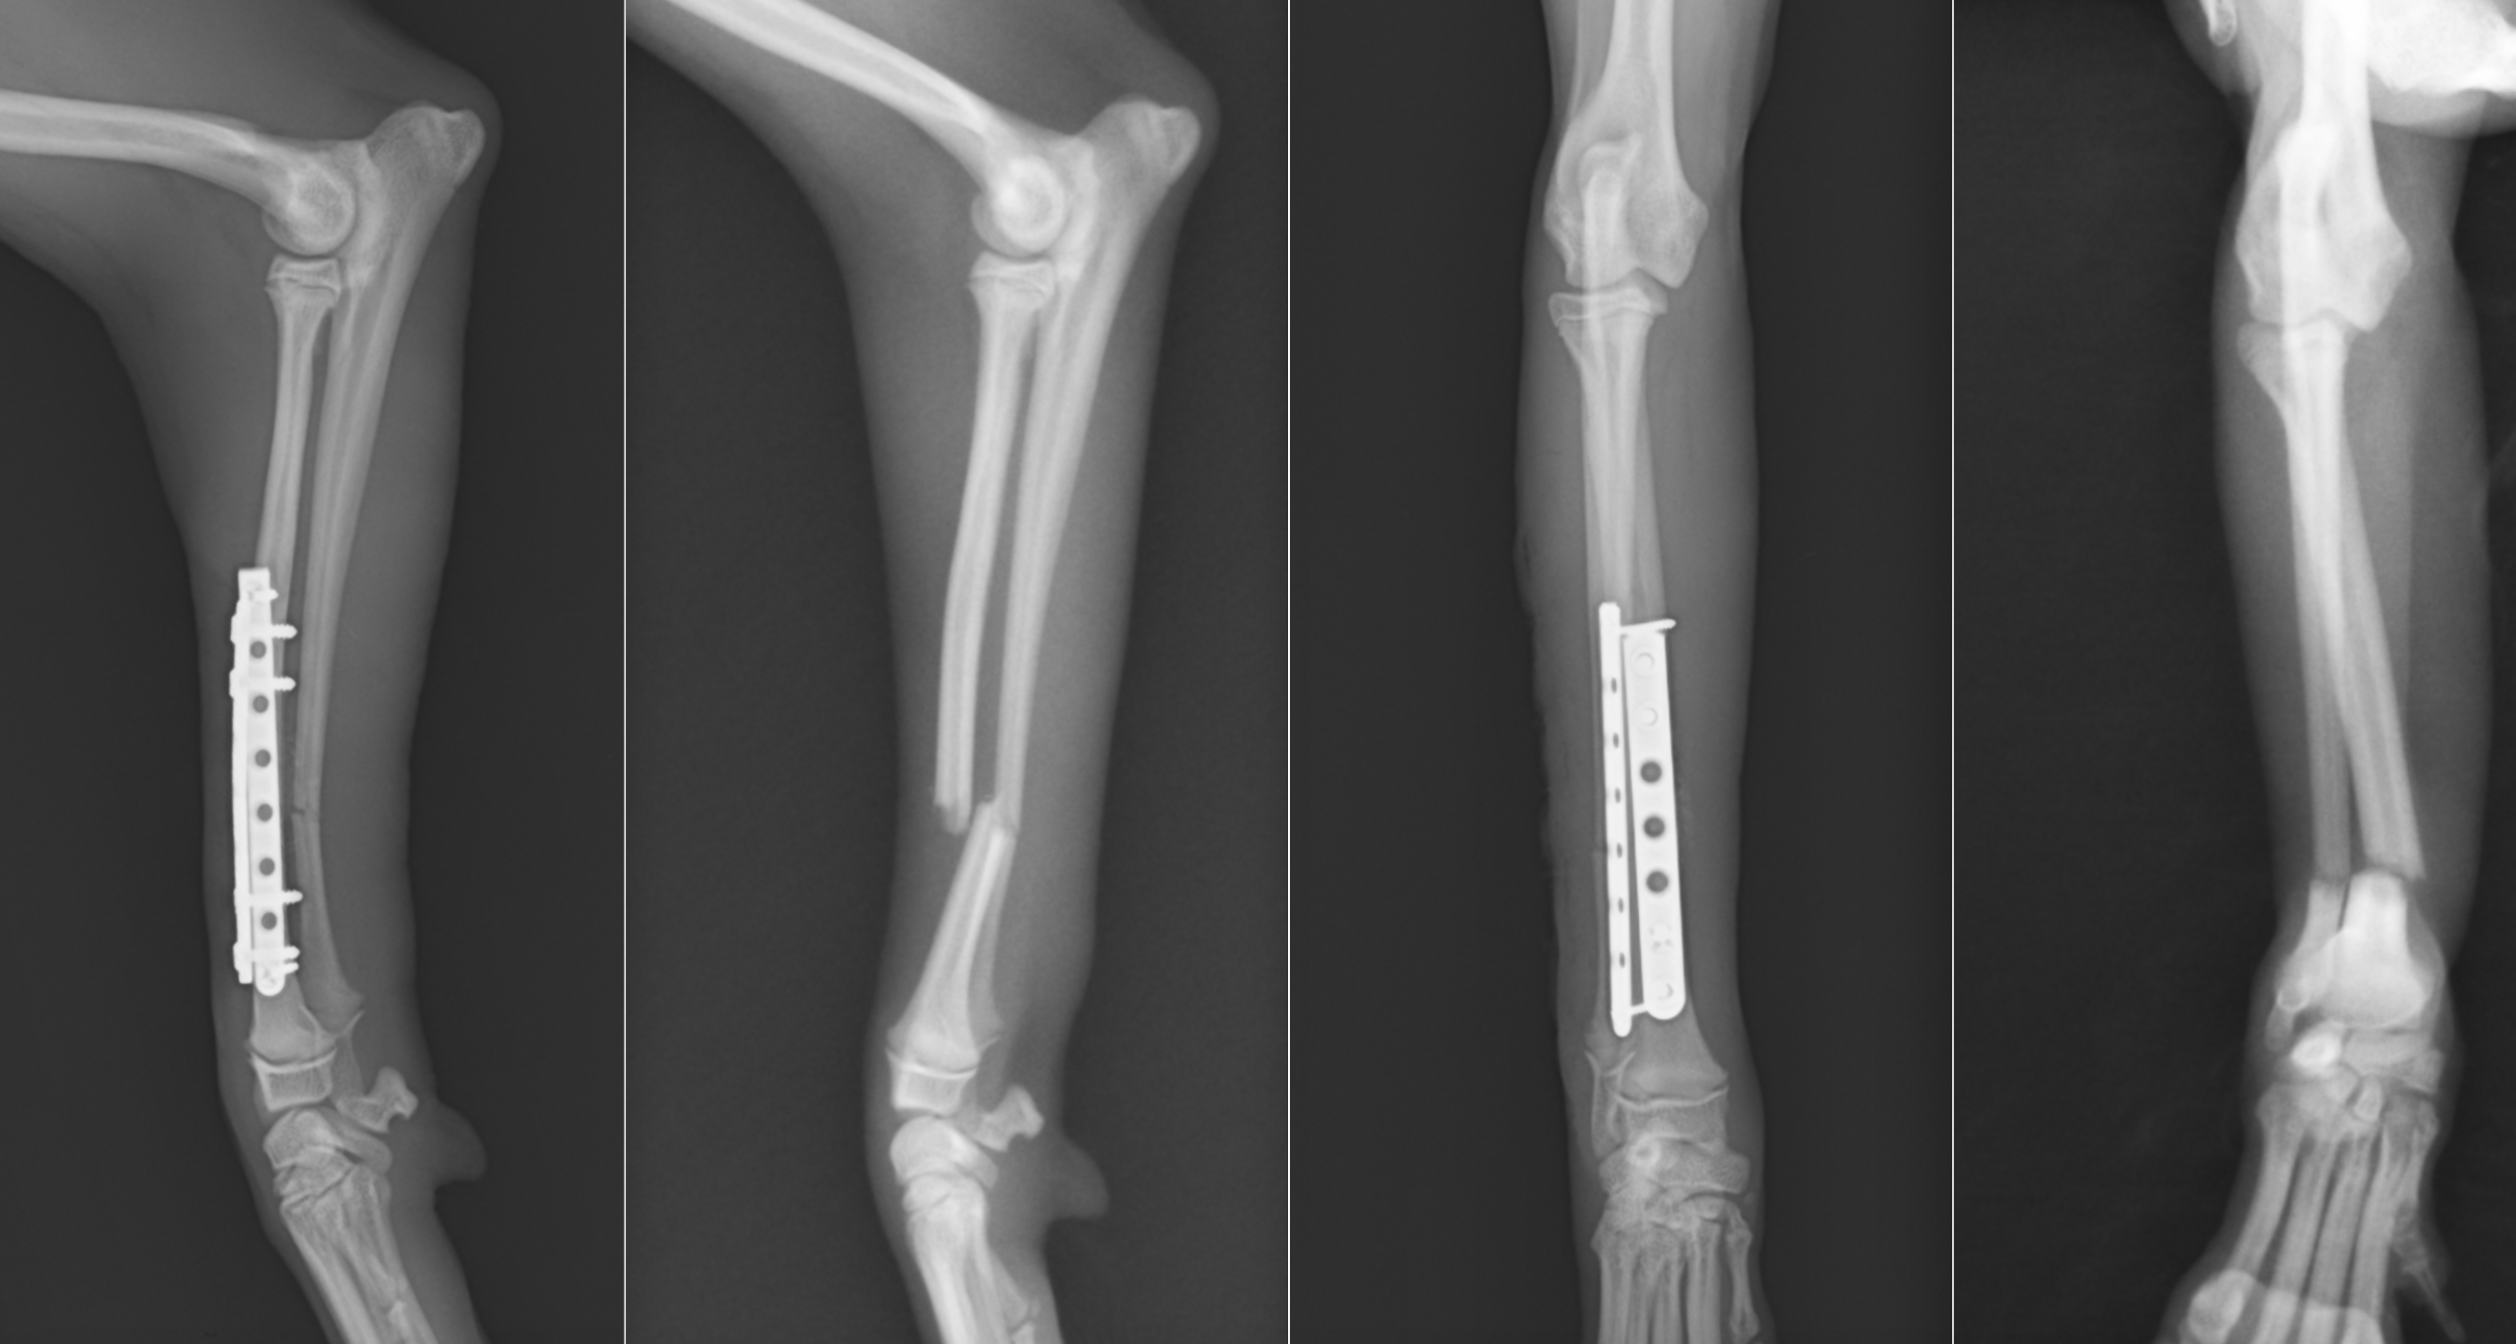

術後のレントゲン写真です。骨折部位はきちんと整復され、アライメント(骨の向き)も真っ直ぐになっています。

今回の子は体重1.7kgで骨も細かったため、1.3mmと1.1mmのプレート・スクリューを選択しました。このように、体重や骨の太さ、活動性に基づきプレートやスクリューを選択し、形に合わせてプレートを曲げたり、捻ったりして骨に合わせていきます。

1週間で退院となりますが、退院時には4本足で歩いて帰れることがほとんどです。2週間後には抜糸となり、28〜42日後には正面のプレートを抜去していきます。そうすることで、プレート抜去後の再骨折を可能な限り最小限にすることが可能となります。